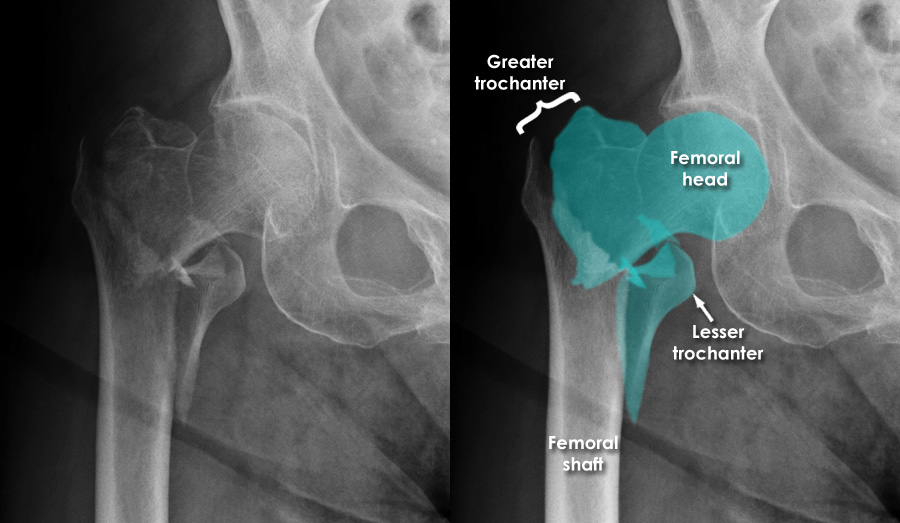

Femoral Neck Hip Fracture Hip Fracture Xray proximal femoral fractures are a subset of fractures that occur in the hip region. They tend to occur in older. The series is requested for a. plain radiography is usually sufficient for diagnosis, but magnetic resonance imaging should be obtained if suspicion of fracture persists despite normal. the hip series is comprised of an anteroposterior (ap) and. Hip Fracture Xray.

From mungfali.com